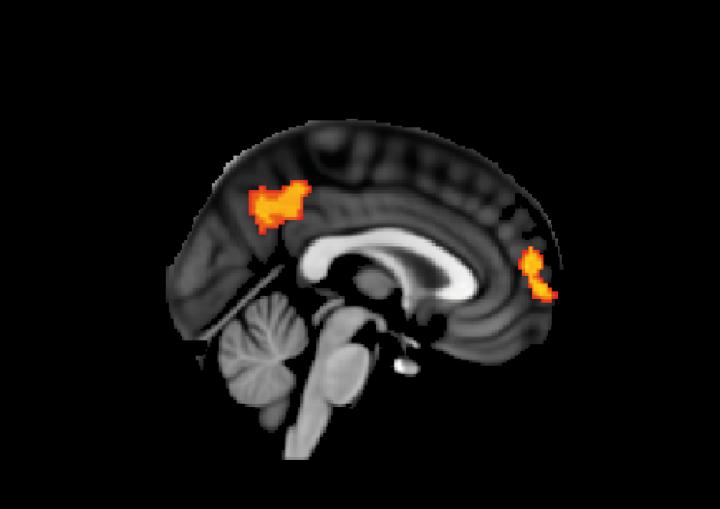

Lucia Li et al. 2019

They found that differences in the makeup of the brain's white matter - the tissue deep in the brain and rich in the branching 'tails' of nerve cells - were key. The research revealed that those who had more connectivity in the regions being stimulated were more likely to respond better to the treatment.

However, when they analysed MRI scans, they found that those participants with highly-connected white matter in the brain region being stimulated responded best to the treatment, and those who had damaged or less-connected regions of white matter showed less improvement.